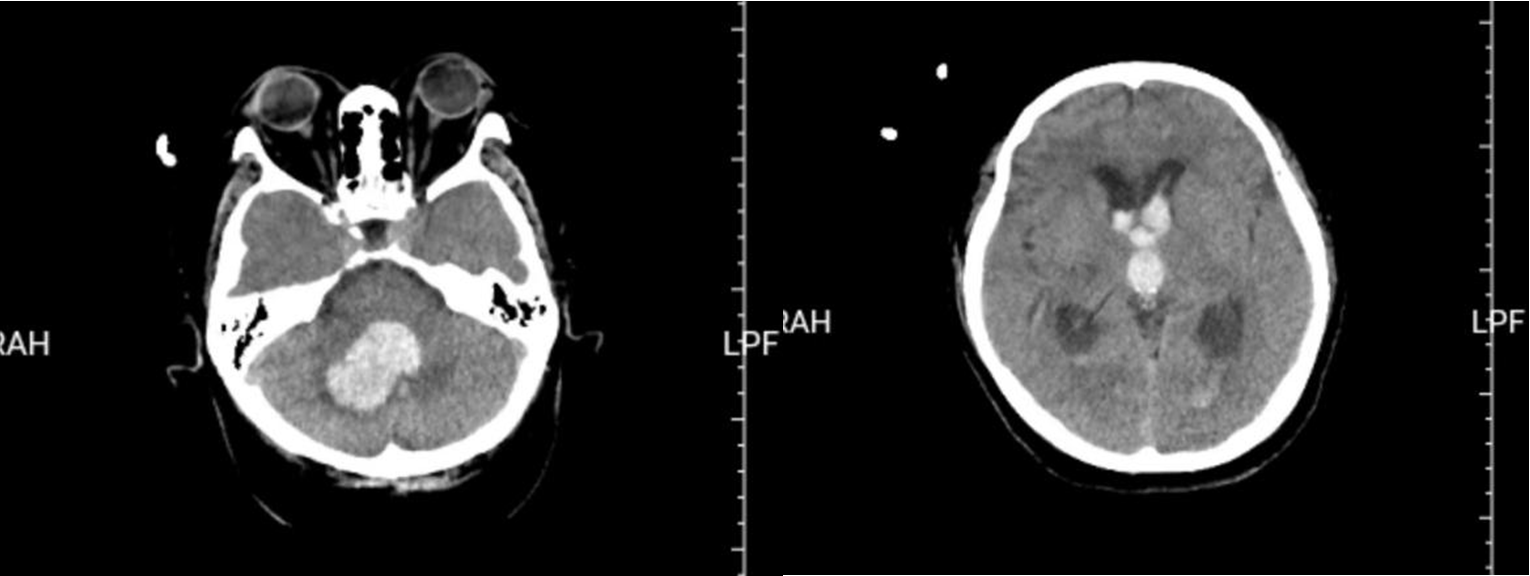

图中所示为患者入院时颅脑CT。

当日,这位患者突然出现肢体活动不灵的情况,并伴有意识障碍、呕吐,随后他被紧急送往烟台山医院东院区。到达急诊科时,他已昏迷,呼吸微弱,接诊医师迅速判断病情,并给予气管插管,但患者身材矮胖,颈部粗短,医师多次尝试气管插管,均未成功。急诊重症监护病房潘继明主任医师当即决定给予患者喉罩置入,并完善颅脑CT等相关检查。CT检查提示:右侧小脑出血并破入脑室,脑室铸型,急性梗阻性脑积水。患者病情危重,进展迅速,逐渐出现血压下降、心率不稳等危急表现,并随时可能出现呼吸心跳骤停。